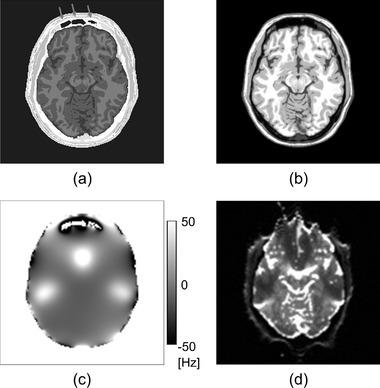

Although echo-planar imaging (EPI) is widely used for diffusion magnetic resonance (MR) imaging, EPI images suffer from susceptibility-induced geometric distortions. We herein propose a new estimation method for undistorted EPI images using anatomical T -weighted images (T WIs) based on the physics of MR imaging.

METHODS

Our proposed method estimates the undistorted EPI image in the image domain while estimating the magnetic field inhomogeneity map using the conjugate gradient method with anatomical regularization. Our method synthesizes the distorted image to match the measured EPI image containing geometric distortions by alternately updating the undistorted EPI image and the magnetic field inhomogeneity map. We evaluated our proposed method and compared it with a nonrigid registration-based distortion correction method using simulated data and using real data. In the evaluation of the estimation of the magnetic field inhomogeneity map, we used the normalized root-mean-squared error (NRMSE) between the estimated results and the ground truth. In the evaluation of the estimation of undistorted images, we used mutual information (MI) between the undistorted EPI image and the anatomical T WI.

虽然平面回波成像(EPI)广泛用于扩散磁共振(MR)成像,但 EPI 图像会受到磁化率引起的几何变形的影响。我们在此提出了一种基于磁共振成像物理原理,使用解剖 T 加权图像(TWI)对无失真 EPI 图像进行估计的新方法。

方法

我们的方法在图像域中估计无失真的 EPI 图像,同时使用带有解剖学正则化的共轭梯度法估计磁场不均匀图。我们的方法通过交替更新无失真的 EPI 图像和磁场不均匀图,合成失真图像以匹配包含几何变形的测量 EPI 图像。我们使用模拟数据和真实数据评估了我们的方法,并将其与基于非刚性配准的失真校正方法进行了比较。在评估磁场不均匀图的估计时,我们使用了估计结果与真实值之间的归一化均方根误差(NRMSE)。在评估无失真图像的估计时,我们使用了无失真 EPI 图像和解剖 TWI 之间的互信息(MI)。